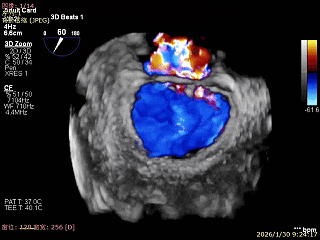

3D Enface 2区及3区前叶脱向左房

3D Enface 可见反流由2区3区从前后冲出

3D Enface下组织桥稳定残余外侧前叶脱垂

3D Enface上彩可见夹子内侧无反流,残余外侧反流

3D Enface下组织桥稳定无反流

夹子释放后,反流基本消失

LVOT切面可见主瓣二尖瓣术后反流基本消失